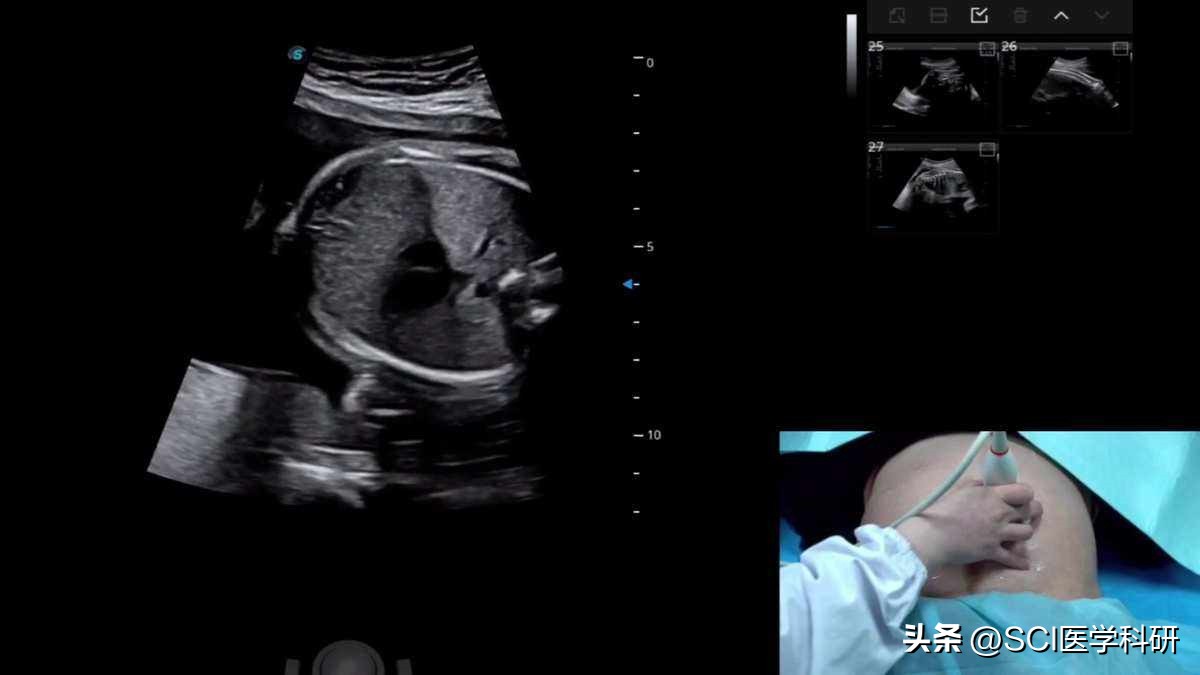

目前常用的筛查和诊断方法主要是通过胎儿超声来筛查出长骨(即肱骨和股骨)短小的ACH可疑胎儿,再对筛查出的ACH可疑胎儿和宫内生长迟缓胎儿进行染色体检查和FGFR3基因检测,完成对可疑胎儿的产前诊断。如果父母亲之一或者双方均为确诊的ACH患者,则可在孕11~13周做胎儿FGFR3基因产前诊断。

目前,绝大多数ACH患儿主要是通过产前超声检查来进行筛查的,许多公认的产前超声检查指标,如相对大的头部和腹部、四肢短小、三叉手、胸腔狭窄、前额突出和羊水过多等,都不是明确的确诊指标。

研究表明,ACH患儿在孕20~24周产前超声检查时肢体长度仍可在正常范围,通常在妊娠26周以后出现典型的异常表现。常规的超声检查在孕中晚期才能观察到胎儿长骨的缩短。ACH患儿比正常患儿在股骨干骺端的骨骺角度宽。ACH患儿的股骨近端干骺端出现圆形、不规则的骨化,骨干异常连接,骨膜相对过度生长,这一新的诊断指征 ,被称为“环圈”的标志。利用胎儿游离DNA可以正确的检测胎儿ACH。